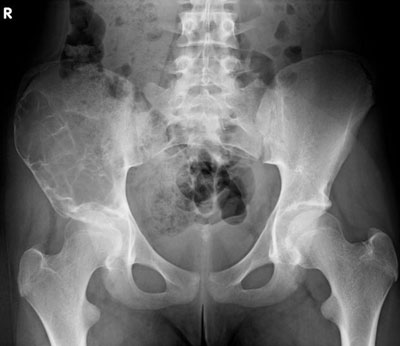

Ein 13-jähriges Mädchen kommt humpelnd zu Ihnen in die Praxis mit Schmerzen in der rechten Hüfte, die seit einigen Monaten bestehen und besonders bei Belastungen auftreten. Eine sichtbare Schwellung besteht nicht, kein Sturzgeschehen in der Anamnese.

Die Röntgenuntersuchung von Becken/Hüfte zeigt eine septierte geographische Osteolyse in der Ala und im Korpus des Os Iliums rechts. Das Röntgenbild und die Aufnahmen der nachfolgenden MRI-Untersuchung sehen Sie hier:

Becken/Hüfte pa

Welche Diagnose stellen sie aufgrund der vorliegenden Bilder?